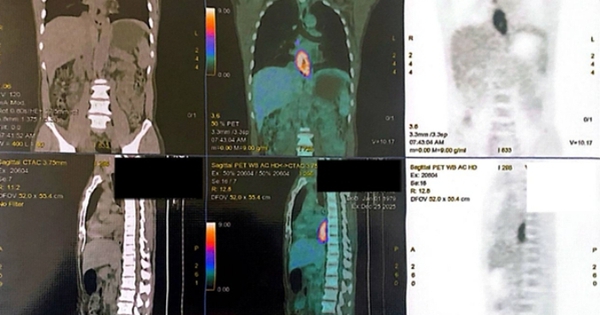

Người đàn ông nhập viện vì nuốt nghẹn, sụt 5 kg trong một tháng, đi khám phát hiện cùng lúc hai ung thư biểu mô vảy ở thực quản và hầu miệng.